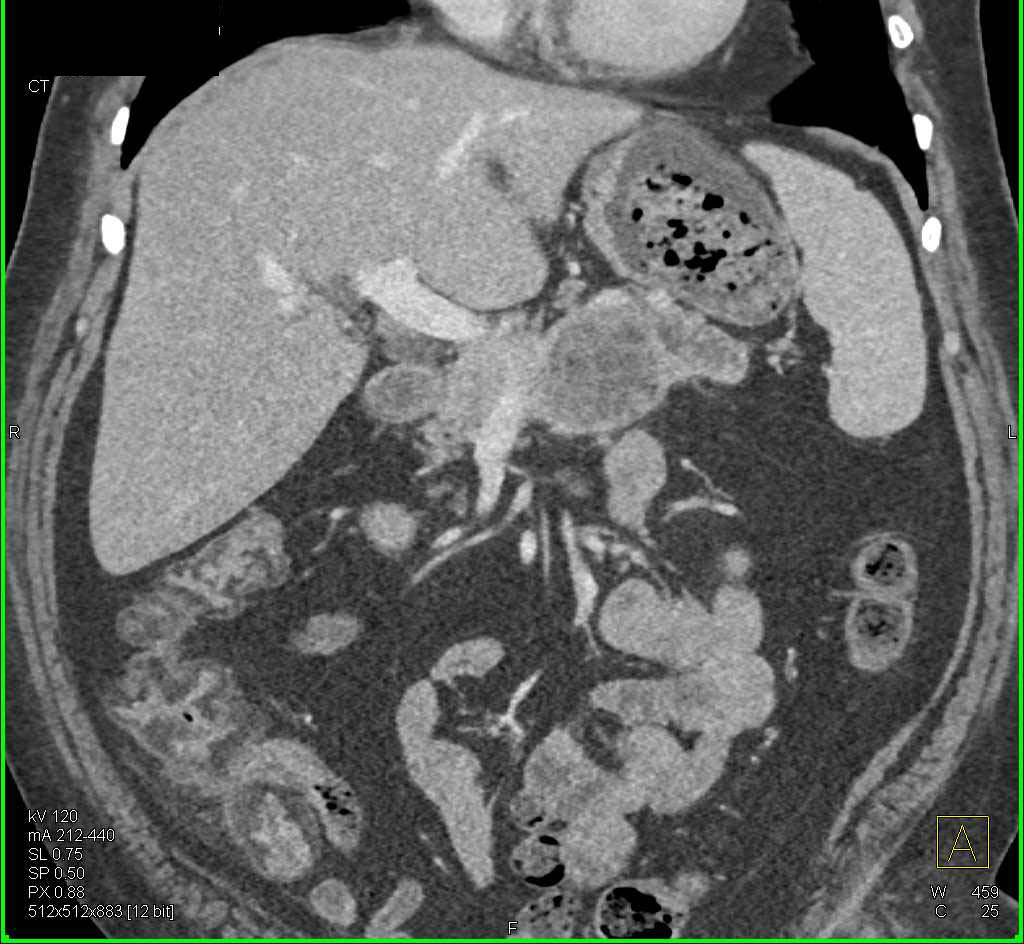

Gastric Adenocarcinoma with Ulcer